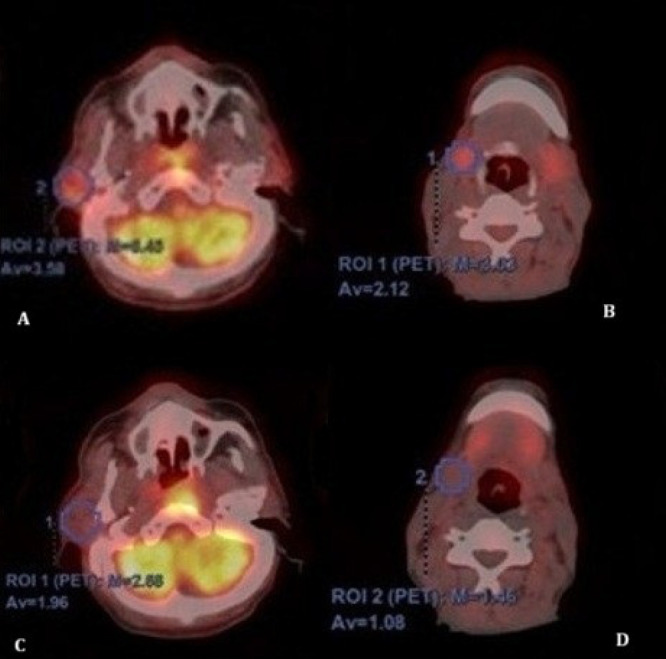

目的:探讨放疗(RT)后放疗剂量、18f -氟脱氧葡萄糖正电子发射断层扫描/计算机断层扫描(18F-FDG PET/CT)评估的唾液腺代谢变化与头颈癌患者口干严重程度的关系。方法:回顾性分析107例接受调强放疗或调容弧线治疗的头颈部恶性肿瘤患者。在治疗后PET/CT检查时评估临床口干严重程度。从治疗方案中提取平均腺体剂量和剂量-体积参数(V10-V50)。通过治疗前后PET/CT扫描的Δmaximum标准化摄取值和Δmean标准化摄取值评估代谢变化。研究了临床、剂量学和代谢变量之间的关系。结果:63.6%的患者出现中重度口干。较高的T和N分期与更严重的口干严重程度显著相关(pΔSUV值与平均剂量和剂量-体积参数显著相关,特别是在左腮腺,接受bbb30 Gy的患者代谢下降明显更大。腮腺比下颌骨腺表现出更强的剂量依赖性代谢变化,这与它们更高的放射敏感性一致。结论:尽管采用了先进的放射治疗技术,但口干仍然是一种常见的毒性。18F-FDG PET/CT可靠地捕获剂量依赖性唾液腺损伤,并反映肿瘤负荷对毒性风险的影响。这些发现强调了pet衍生的生物标志物作为预测常规剂量学参数之外的唾液功能障碍的综合工具的补充作用。

Methods: We retrospectively analyzed 107 patients treated with intensity-modulated RT or volumetric modulated arc therapy for head and neck malignancies. Clinical xerostomia severity was evaluated at the time of post-treatment PET/CT. Mean gland doses and dose-volume parameters (V10-V50) were extracted from treatment plans. Metabolic changes were evaluated by Δmaximum standardized uptake value and Δmean standardized uptake value between pre and post treatment PET/CT scans. The relationships between clinical, dosimetric, and metabolic variables were examined.

Results: Moderate-to-severe xerostomia occurred in 63.6% of patients. Both higher T and N stage were significantly associated with greater xerostomia severity (p<0.05). Patients with nodal metastases on pretreatment PET/CT demonstrated a higher prevalence of xerostomia. Dose-volume parameters (V10-V30 for parotids, V50 for submandibular glands) were significantly correlated with symptom severity. ΔSUV values were significantly associated with both mean dose and dose-volume parameters, particularly in the left parotid gland, where patients receiving >30 Gy showed markedly greater metabolic decline. Parotid glands demonstrated stronger dose-dependent metabolic changes compared with submandibular glands, consistent with their higher radiosensitivity.